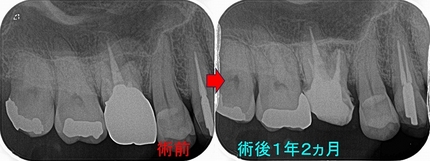

レントゲンを撮ると

はっきり根尖病変写っているんですけど・・・

過去に抜髄をしているようですが、4根管中1根(口蓋根)しか治療していない感じ

治療は2回で仕上げました。

病変の原因と思われる、MB,MB2もガッタパーチャー使用

そこから、1年後

病変は殆ど無くなってきています